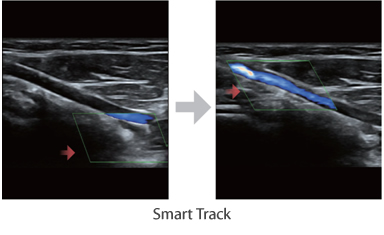

–ú–Ĺ–ĺ–≥–ĺ—Ą—É–Ĺ–ļ—Ü–ł–ĺ–Ĺ–į–Ľ—Ć–Ĺ–į—Ź —Ā–ł—Ā—ā–Ķ–ľ–į DC-60 Exp —Ā X-Insight –Ņ—Ä–Ķ–ī—Ā—ā–į–≤–Ľ—Ź–Ķ—ā —Ā–ĺ–Ī–ĺ–Ļ –ļ–ĺ–ľ–Ņ–Ľ–Ķ–ļ—Ā–Ĺ–ĺ–Ķ —Ä–Ķ—ą–Ķ–Ĺ–ł–Ķ, –ļ–ĺ—ā–ĺ—Ä–ĺ–Ķ –Ņ–ĺ–ľ–ĺ–≥–į–Ķ—ā —É–Ņ—Ä–į–≤–Ľ—Ź—ā—Ć –Ņ–ĺ–≤—Ā–Ķ–ī–Ĺ–Ķ–≤–Ĺ–ĺ–Ļ –ļ–Ľ–ł–Ĺ–ł—á–Ķ—Ā–ļ–ĺ–Ļ –Ņ—Ä–į–ļ—ā–ł–ļ–ĺ–Ļ —Ā –Ľ–Ķ–≥–ļ–ĺ—Ā—ā—Ć—é –ł —É–≤–Ķ—Ä–Ķ–Ĺ–Ĺ–ĺ—Ā—ā—Ć—é.

–ě—Ā–Ĺ–ĺ–≤—č–≤–į—Ź—Ā—Ć –Ĺ–į –≥–Ľ—É–Ī–ĺ–ļ–ĺ–ľ –Ņ–ĺ–Ĺ–ł–ľ–į–Ĺ–ł–ł –Ņ–ĺ—ā—Ä–Ķ–Ī–Ĺ–ĺ—Ā—ā–Ķ–Ļ –ļ–Ľ–ł–Ķ–Ĺ—ā–ĺ–≤, –ļ–ĺ–ľ–Ņ–į–Ĺ–ł—Ź Mindray —Ä–į–∑—Ä–į–Ī–ĺ—ā–į–Ľ–į —Ā–ł—Ā—ā–Ķ–ľ—É DC-60 Exp —Ā X-Insight, —á—ā–ĺ–Ī—č –ĺ–Ī–Ķ—Ā–Ņ–Ķ—á–ł—ā—Ć –≤—č—Ā–ĺ–ļ—É—é –Ņ—Ä–ĺ–ł–∑–≤–ĺ–ī–ł—ā–Ķ–Ľ—Ć–Ĺ–ĺ—Ā—ā—Ć –ł —ā–ĺ—á–Ĺ–ĺ—Ā—ā—Ć –≤–ł–∑—É–į–Ľ–ł–∑–į—Ü–ł–ł –≤–ļ—É–Ņ–Ķ —Ā –Ĺ–į–≥–Ľ—Ź–ī–Ĺ–ĺ—Ā—ā—Ć—é, –ł—Ā–ļ–Ľ—é—á–ł—ā–Ķ–Ľ—Ć–Ĺ–ĺ–Ļ –ł–Ĺ—ā–Ķ–Ľ–Ľ–Ķ–ļ—ā—É–į–Ľ—Ć–Ĺ–ĺ—Ā—ā—Ć—é –ł –ĺ–≥—Ä–ĺ–ľ–Ĺ—č–ľ –ĺ–Ņ—č—ā–ĺ–ľ.